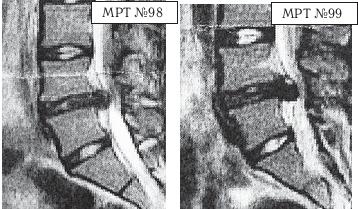

На МРТ № 98 у той же пациентки наблюдается послеоперационный рецидив грыжи межпозвонкового диска в сегменте LIV—LV

На МРТ № 99 у той же пациентки наблюдается рецидив после двух операций, секвестрированная грыжа межпозвонкового диска LIV—LV

Этот случай, к сожалению, далеко не единственный. У данной пациентки, молодой девушки, впервые появились боли в поясничном отделе позвоночника в возрасте 15 лет. Родители обратились в районную больницу, где девушку пролечили медикаментозно. Боли прошли. Практически полгода она чувствовала себя хорошо. После физической нагрузки боли возобновились. Но на этот раз родители, поддавшись рекламе, решили вместо районной больницы обратиться в частный медицинский центр. Девушку осмотрел врач и, не удосужившись отправить пациентку на диагностическое обследование, просто предложил родителям приобрести в данном медцентре специальное приспособление для вытяжения позвоночника под собственным весом (с регулируемым углом наклона по отношению к полу и регулируемым положением ручек захвата на нём для рук). Вдобавок к этому приспособлению в медцентре выдали обучающую брошюру с описанием комплекса силовых упражнений на этом устройстве для укрепления мышечного корсета и на этом их «лечение» закончилось. Первое время занятий на данном приспособлении действительно давали девушке временное облегчение. Но вскоре начался обратный эффект.